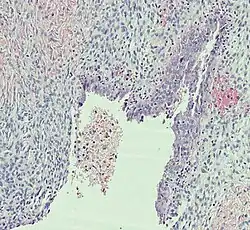

Histopathology

In case an ovarian cyst is surgically removed, a more definite diagnosis can be made by histopathology:

| Type | Subtype | Typical microscopy findings | Image |

| Cystadenoma | Serous cystadenoma | Cyst lining consisting of a simple epithelium, whose cells may be either:[26]

|